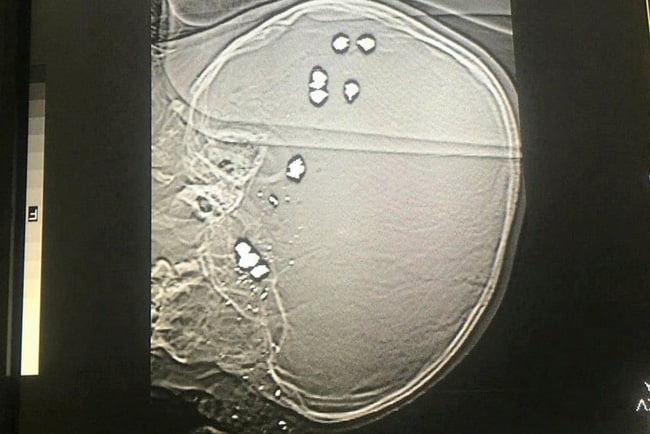

| Hình ảnh những viên đạn găm vào đầu bé trai 6 tuổi dẫn tới tử vong |

Theo thông tin ban đầu, khoảng 11 giờ 26 phút ngày 29-3, Bệnh viên sản nhi Ninh Bình tiếp nhận bé trai B.T.P. (6 tuổi, ngụ huyện Lạc Thủy, tỉnh Hòa Bình) nhập viện trong tình trạng hôn mê sâu, suy hô hấp, mất nhiều máu, trong đầu có 11 viên đạn bi.